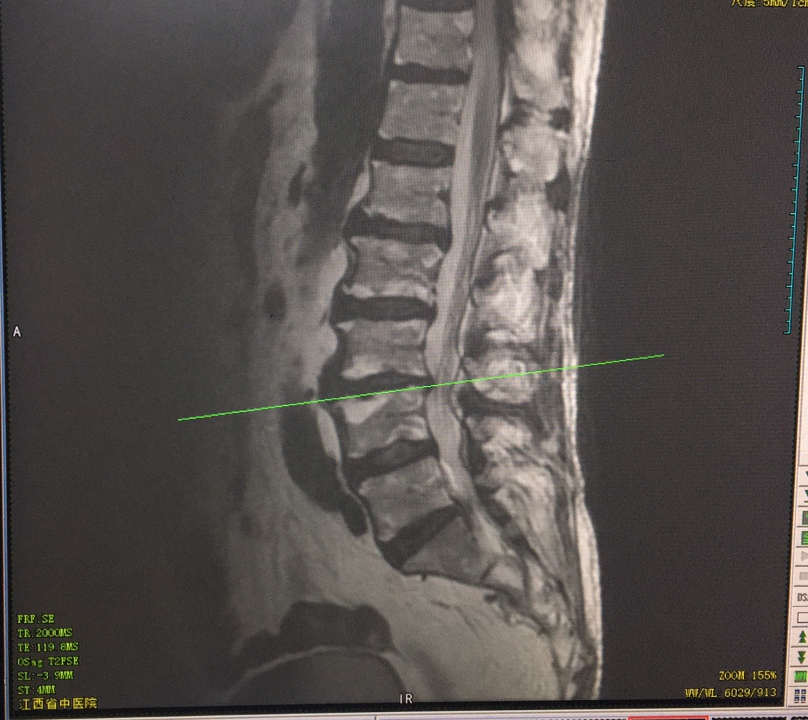

術前影像學

(圖示:MRI示:L3/4椎管狹窄)